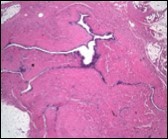

Alternatively, cutaneous ciliated cyst can be lined by non ciliated cuboidal or columnar epithelium with intermingled intercalated, dark or round peg cells. Foci of squamous metaplasia can be occasionally exemplified in the adherent epithelium whereas mucinous cells or apocrine-like features are exceptional 6, 8. Figure 1, Figure 2, Figure 3, Figure 4, Figure 5, Figure 6, Figure 7, Figure 8, Figure 9, Figure 10, Figure 11, Figure 12. 11, 12, 13, 14, 15, 16, 17, 18, 19.

Figure 1.Ciliated cutaneous cyst lined by pseudostratified ciliated columnar epithelium and a supporting fibro-connective tissue stroma 11.